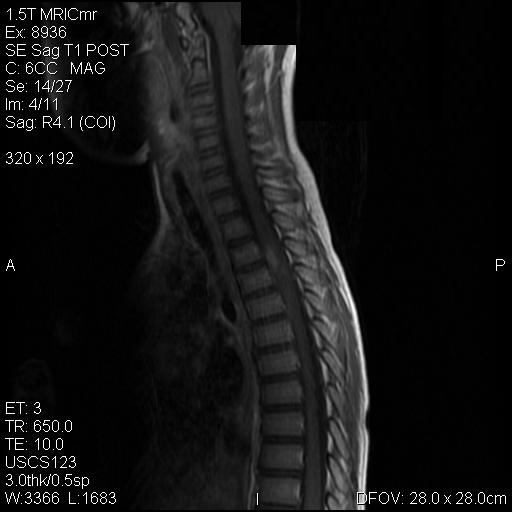

Representative images from the MR studies and specimen are illustrated below:

A. T1 |

B. T1+Contrast |

C. T1+Contrast |

D. T2 |

E. T1+Contrast |

Panel A to E are MR images. Panel F and G are taken from intraoperative cytologic preparation. Panel H to M are taken from frozen section. Panel N and O are from paraffin section. These sections are stained by hematoxylin-eosin stain. Panel P is immunohistochemistry for neurofilament proteins. Panel Q is stained by Luxol fast blue-Periodic acid Schiff (LFB-PAS) stain.

MR Imaging:

The segment of spinal cord at T3-T4 level is expanded and is accompanied by edema that runs from T2-T6. The expansion and edema is roughly symmetrical along the long axis of the cord. The expanded levels are isointense to the white matter of the spinal cord on T1-weighed images (Panel A). The edema is best demonstrated on T-weighed images (Panel B, C, and E). Patchy and poorly defined enhancement is demonstrated in the expanded areas (Panel D). The remaining levels of the spinal cord and the brain are free of abnormal changes.